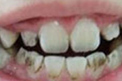

3D仿生全瓷牙

快速解决以下牙齿问题 龅牙、虎牙、老鼠牙、氟斑牙、牙齿拥挤、四环素牙、畸形牙、牙齿稀疏

该术以泰康拜博口腔的3-3-4-4黄金美齿法则漫步在国际齿科美容界,具有快速正畸,美齿、矫正、治齿一步到位的功效。并且,突破 传统美牙冠的弊端,将德国VITA比色术,美国微痛术和口腔内窥镜数码定位有机结合。

技术特点:技术特点:① 高效快速 仅需7天; ② 无需拔牙; ③ 过程舒适; ④ 美齿、矫正、治齿一步到位